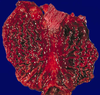

grade this disease

what is found in micro

low grade dysplasia of Barrett’s esophagus

loss of cell polarity, but nuclei still mostly basal

some gland architectural irregularity => mostly not branched or back-to-back